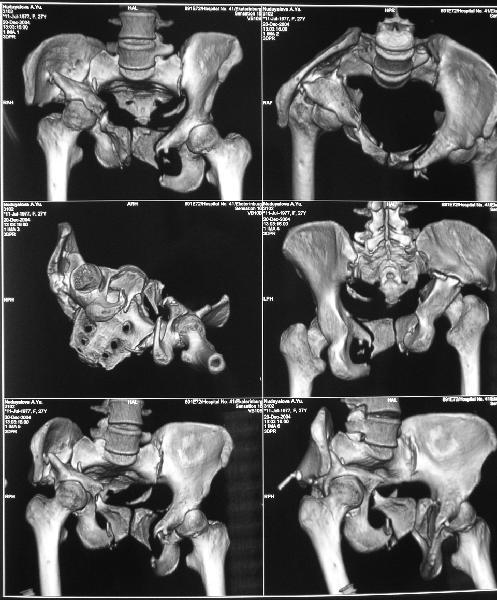

Снимки до лечения: